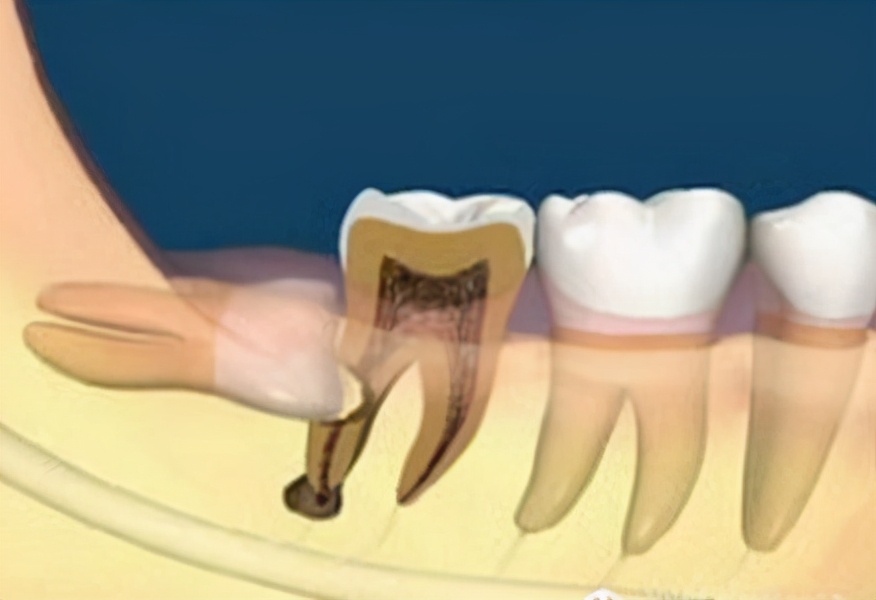

萌出异常的智齿,建议是在还没症状之前,进行干预性拔除,才能避免发炎所带来的疼痛;而如果智齿已经发炎了,是不可以立即拔除的需要先消炎后才能拔除。(动图为拔智齿过程)